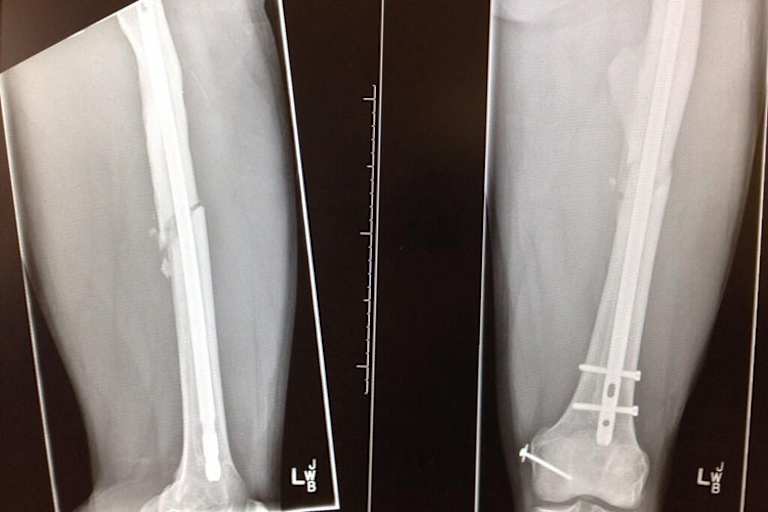

"Ich werde erst zurückkommen, wenn die Zeit reif ist und ich physisch wieder auf einem guten Level bin", kündigte Rea nach seiner Operation Ende August in Koblenz an – und er hält sich auch daran: Auf ein Comeback beim Saisonfinale der Superbike-WM in Jerez de la Frantera wird der Familienvater verzichten. Nach seinem Oberschenkelbruch (links) war die Saison 2013 für den Briten ohnehin gelaufen.